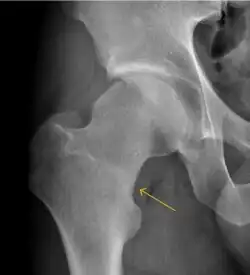

Plain radiography allows us to categorize the hip as normal or dysplastic or with impingement signs (pincer, cam, or a combination of both). Besides these, pathologic processes like osteoarthritis, inflammatory diseases, infection, or tumors can also be identified (Figure 1).[1]

Figure 1.

-

Radiography in normal hip -

X-ray in pincer impingement type of hip dysplasia -

X-ray of cam -

Hip in osteoarthritis -

Septic arthritis